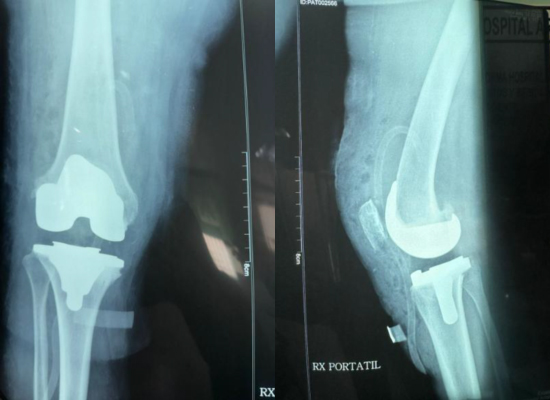

Postoperative Images

4

AP view showing proper implant alignment

5

Lateral view demonstrating bone healing

The patient's knee joint alignment was restored, and joint function improved significantly after surgery. Postoperative follow-up showed stable implant positioning and excellent range of motion recovery.